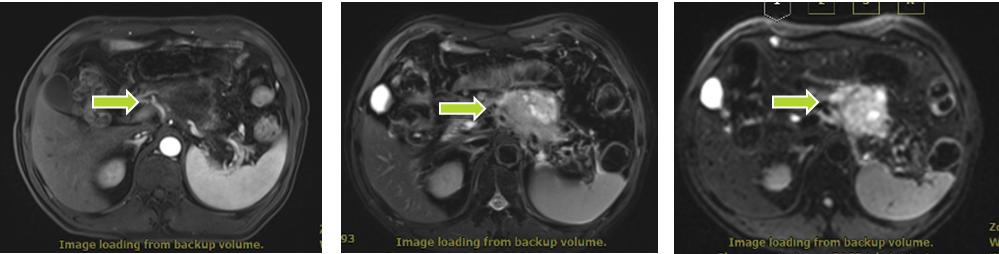

王XX,男,81岁,主诉:上腹部胀痛3月。入院评估:腹部核磁:胰体部肿块(5.4x4.7cm),考虑肿瘤性病变,胰腺癌可能,脾动脉局部包绕,邻近胃小弯受累待排。临床诊断:胰体部腺癌。

碳离子治疗前胰腺癌病灶(5.4x4.7cm)

2021-6-24日开始碳离子治疗,共12次。治疗第5次,疼痛开始缓解,治疗结束后疼痛消失。治疗后3月胰腺病灶明显缩小,治疗后9个月胰体肿瘤消失。患者治疗过程舒适,正常进食,且疼痛缓解快,治疗效果显著。